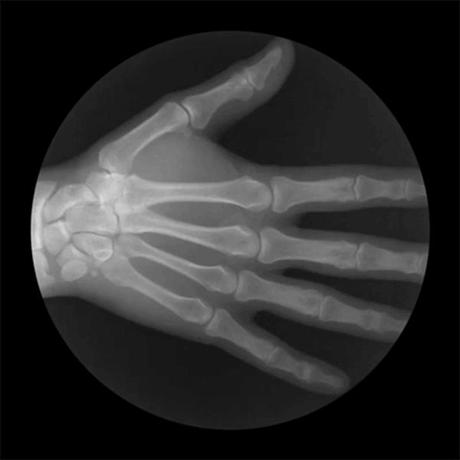

En este Gif vemos el movimiento de la mano y la muñeca.